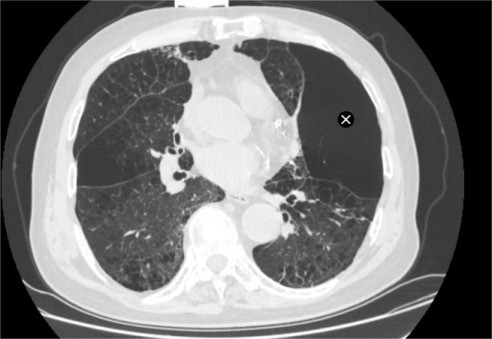

家属带着陈大爷辗转求医,来到苏州大学附属第四医院呼吸内科蒋军红主任门诊就诊。完善胸部CT检查后显示,陈大爷患有异质性肺气肿,肺部病变区域分布极不均衡,部分肺叶过度充气、丧失正常通气功能,形成“无效通气腔”,进一步加重了正常肺组织的负担,这也是他经药物治疗后仍无法缓解症状的核心原因。

手术当天,蒋军红主任和曾大雄主任密切配合,用时30分钟便顺利完成手术。手术通过微创支气管镜介入,在高清内镜视野下,精准定位病变最严重的靶肺叶支气管,精准植入一枚微型支气管内活瓣(EBV-TS-5.5),术中实时验证活瓣开合状态良好,通气单向引流功能正常。